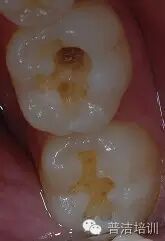

1、评估牙体情况,患牙牙合面形态完整,可直接制作印章,若形成了破坏,可适当做一些形态补偿。

2、牙体颜色较为正常,简单比色后选用3M  Z350 body A3.5色,直接充填 。

Z350树脂制作印章

要点:

1、有效隔湿,棉卷或橡皮障。

2 、轻吹牙面。

3 、印章应覆盖所有需恢复形态的牙面。

4 、印章需要有一定的厚度,否者易变性或取出时折裂。

固化 光照时间要够,充分固化

印章完成 用探针将印章取下,接触面涂布凡士林,若飞边较多,可作适当修整